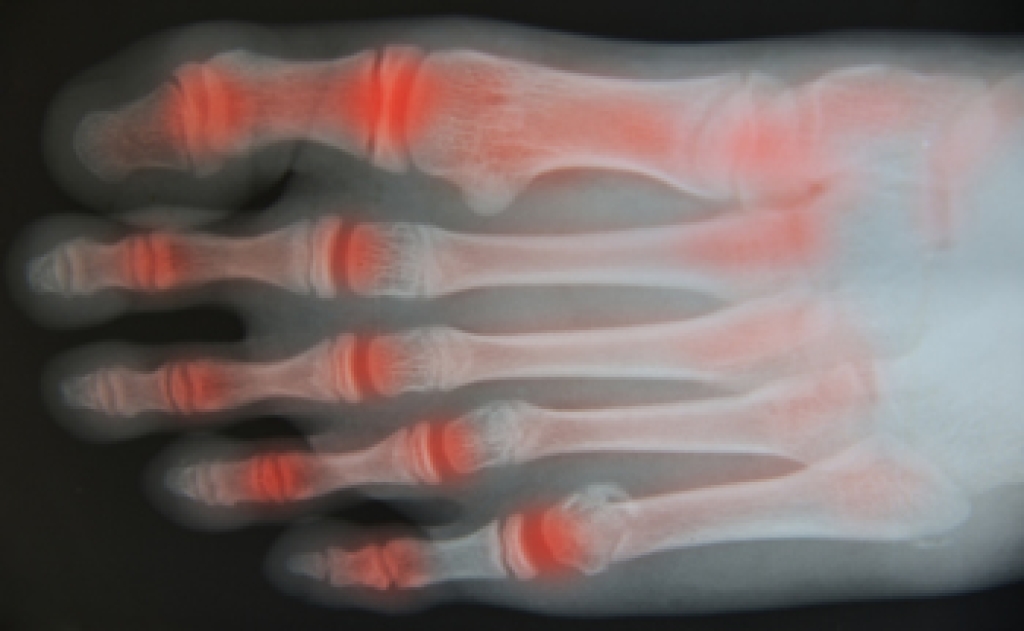

Osteoarthritis is a degenerative joint condition that occurs when cartilage wears down over time, leading to pain and stiffness. In the feet, it often affects joints in the toes and midfoot, making walking uncomfortable. Causes include aging, excess body weight, genetic predisposition, and other forms of arthritis that contribute to joint damage. Symptoms include pain, swelling in foot joints, reduced flexibility, and discomfort that may worsen at night. Persistent foot pain can interfere with daily activities and overall quality of life. A podiatrist can diagnose the condition, recommend supportive footwear, provide custom orthotics, and develop a treatment plan to reduce pain and improve mobility. If you are experiencing ongoing foot discomfort or swelling, it is suggested that you consult a podiatrist who can offer effective relief and management solutions.

Arthritis is a joint disorder that involves the inflammation of different joints in your body, such as those in your feet. Arthritis is often caused by a degenerative joint disease and causes mild to severe pain in all affected areas. In addition to this, swelling and stiffness in the affected joints can also be a common symptom of arthritis.

In many cases, wearing ill-fitting shoes can worsen the effects and pain of arthritis. Wearing shoes that have a lower heel and extra room can help your feet feel more comfortable. In cases of rheumatoid arthritis, the arch in your foot may become problematic. Buying shoes with proper arch support that contour to your feet can help immensely.